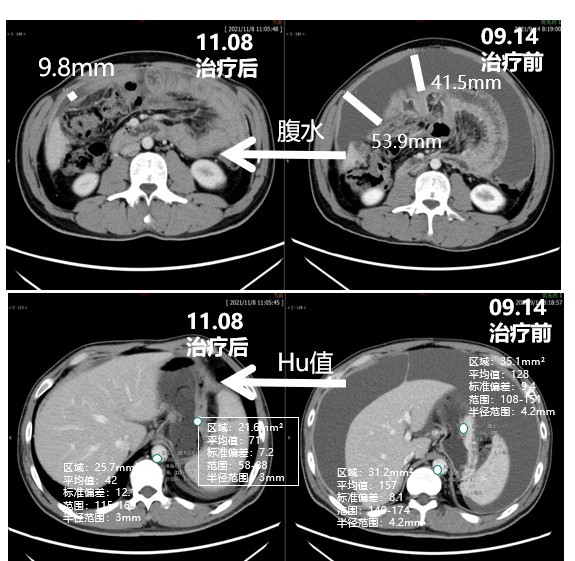

2. 腹水显著减少;患者体感、生活质量显著改善

腹水显著减少